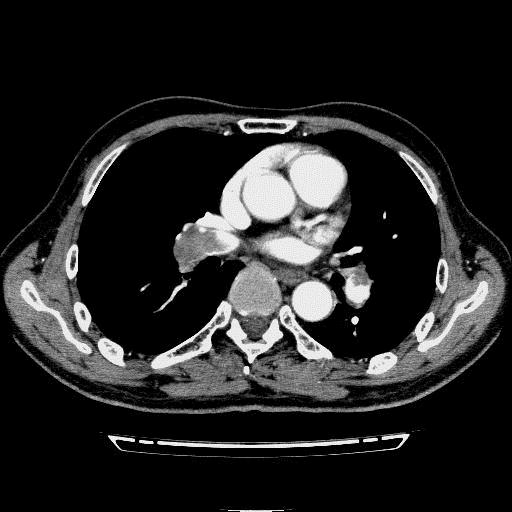

问题 病历摘要: 患者女性,83岁,活动后气促10天,伴心悸、咳嗽,咳少许白粘痰,感左侧胸痛,呈压榨样,与呼吸有关,但无放射痛,并发热,体温最高37.9℃,无明显规律性,无咯血、畏寒等。既往有系统性红斑狼疮病史,有吸烟史20年,已经戒烟20年。1月前始自觉双下肢易疲劳,但活动不受限。体查:T37.7℃,左肺可闻及啸鸣音和少许细湿啰音,心率123bpm,律齐,P2>A2,未闻及杂音。双下肢无水肿。 该病例最可能的诊断是哪种疾病? 提示:胸部 CT平扫+增强见图

选项 A.细菌性肺炎 B.肺癌 C.支气管扩张 D.肺结核并感染 E.主动脉夹层 F.肺动脉高压 G.肺血栓栓塞症

答案 G